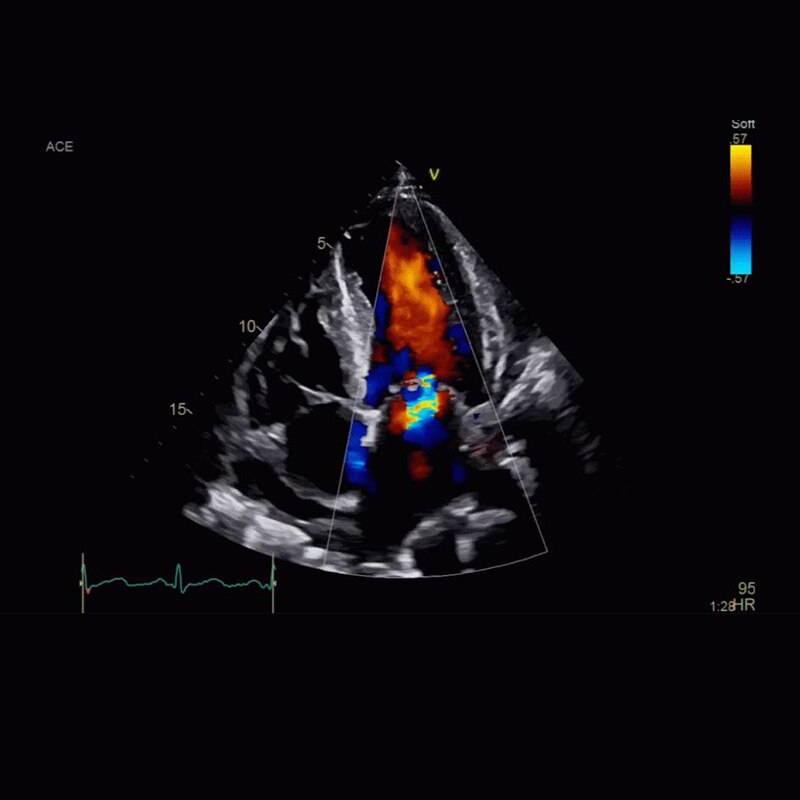

Vivid Portfolio

Cardiac Auto Doppler automatically provides Doppler measurement results for the most common parameters, with minimal user guidance.  Read More

Vivid E95

cSound™ beamforming technology for exceptional visualization quality with impressive resolution in 2D, color flow, Doppler and 4D formats. Read More

VividTM Family Cardiac Ultrasound Automated Function Imaging (AFI)

Assess left ventricular function and cardiac performance with clarity, improving clinical confidence. Read More

Vivid Family Cardiac Ultrasound

Vivid E95 with cSound performance makes 4D as easy as 2D to quantify left ventricular wall motion. Read More

Vivid™ Family Cardiac Ultrasound with Automated Quantification

Assess left ventricular function and cardiac performance with clarty,improving clinical confidence.Read More